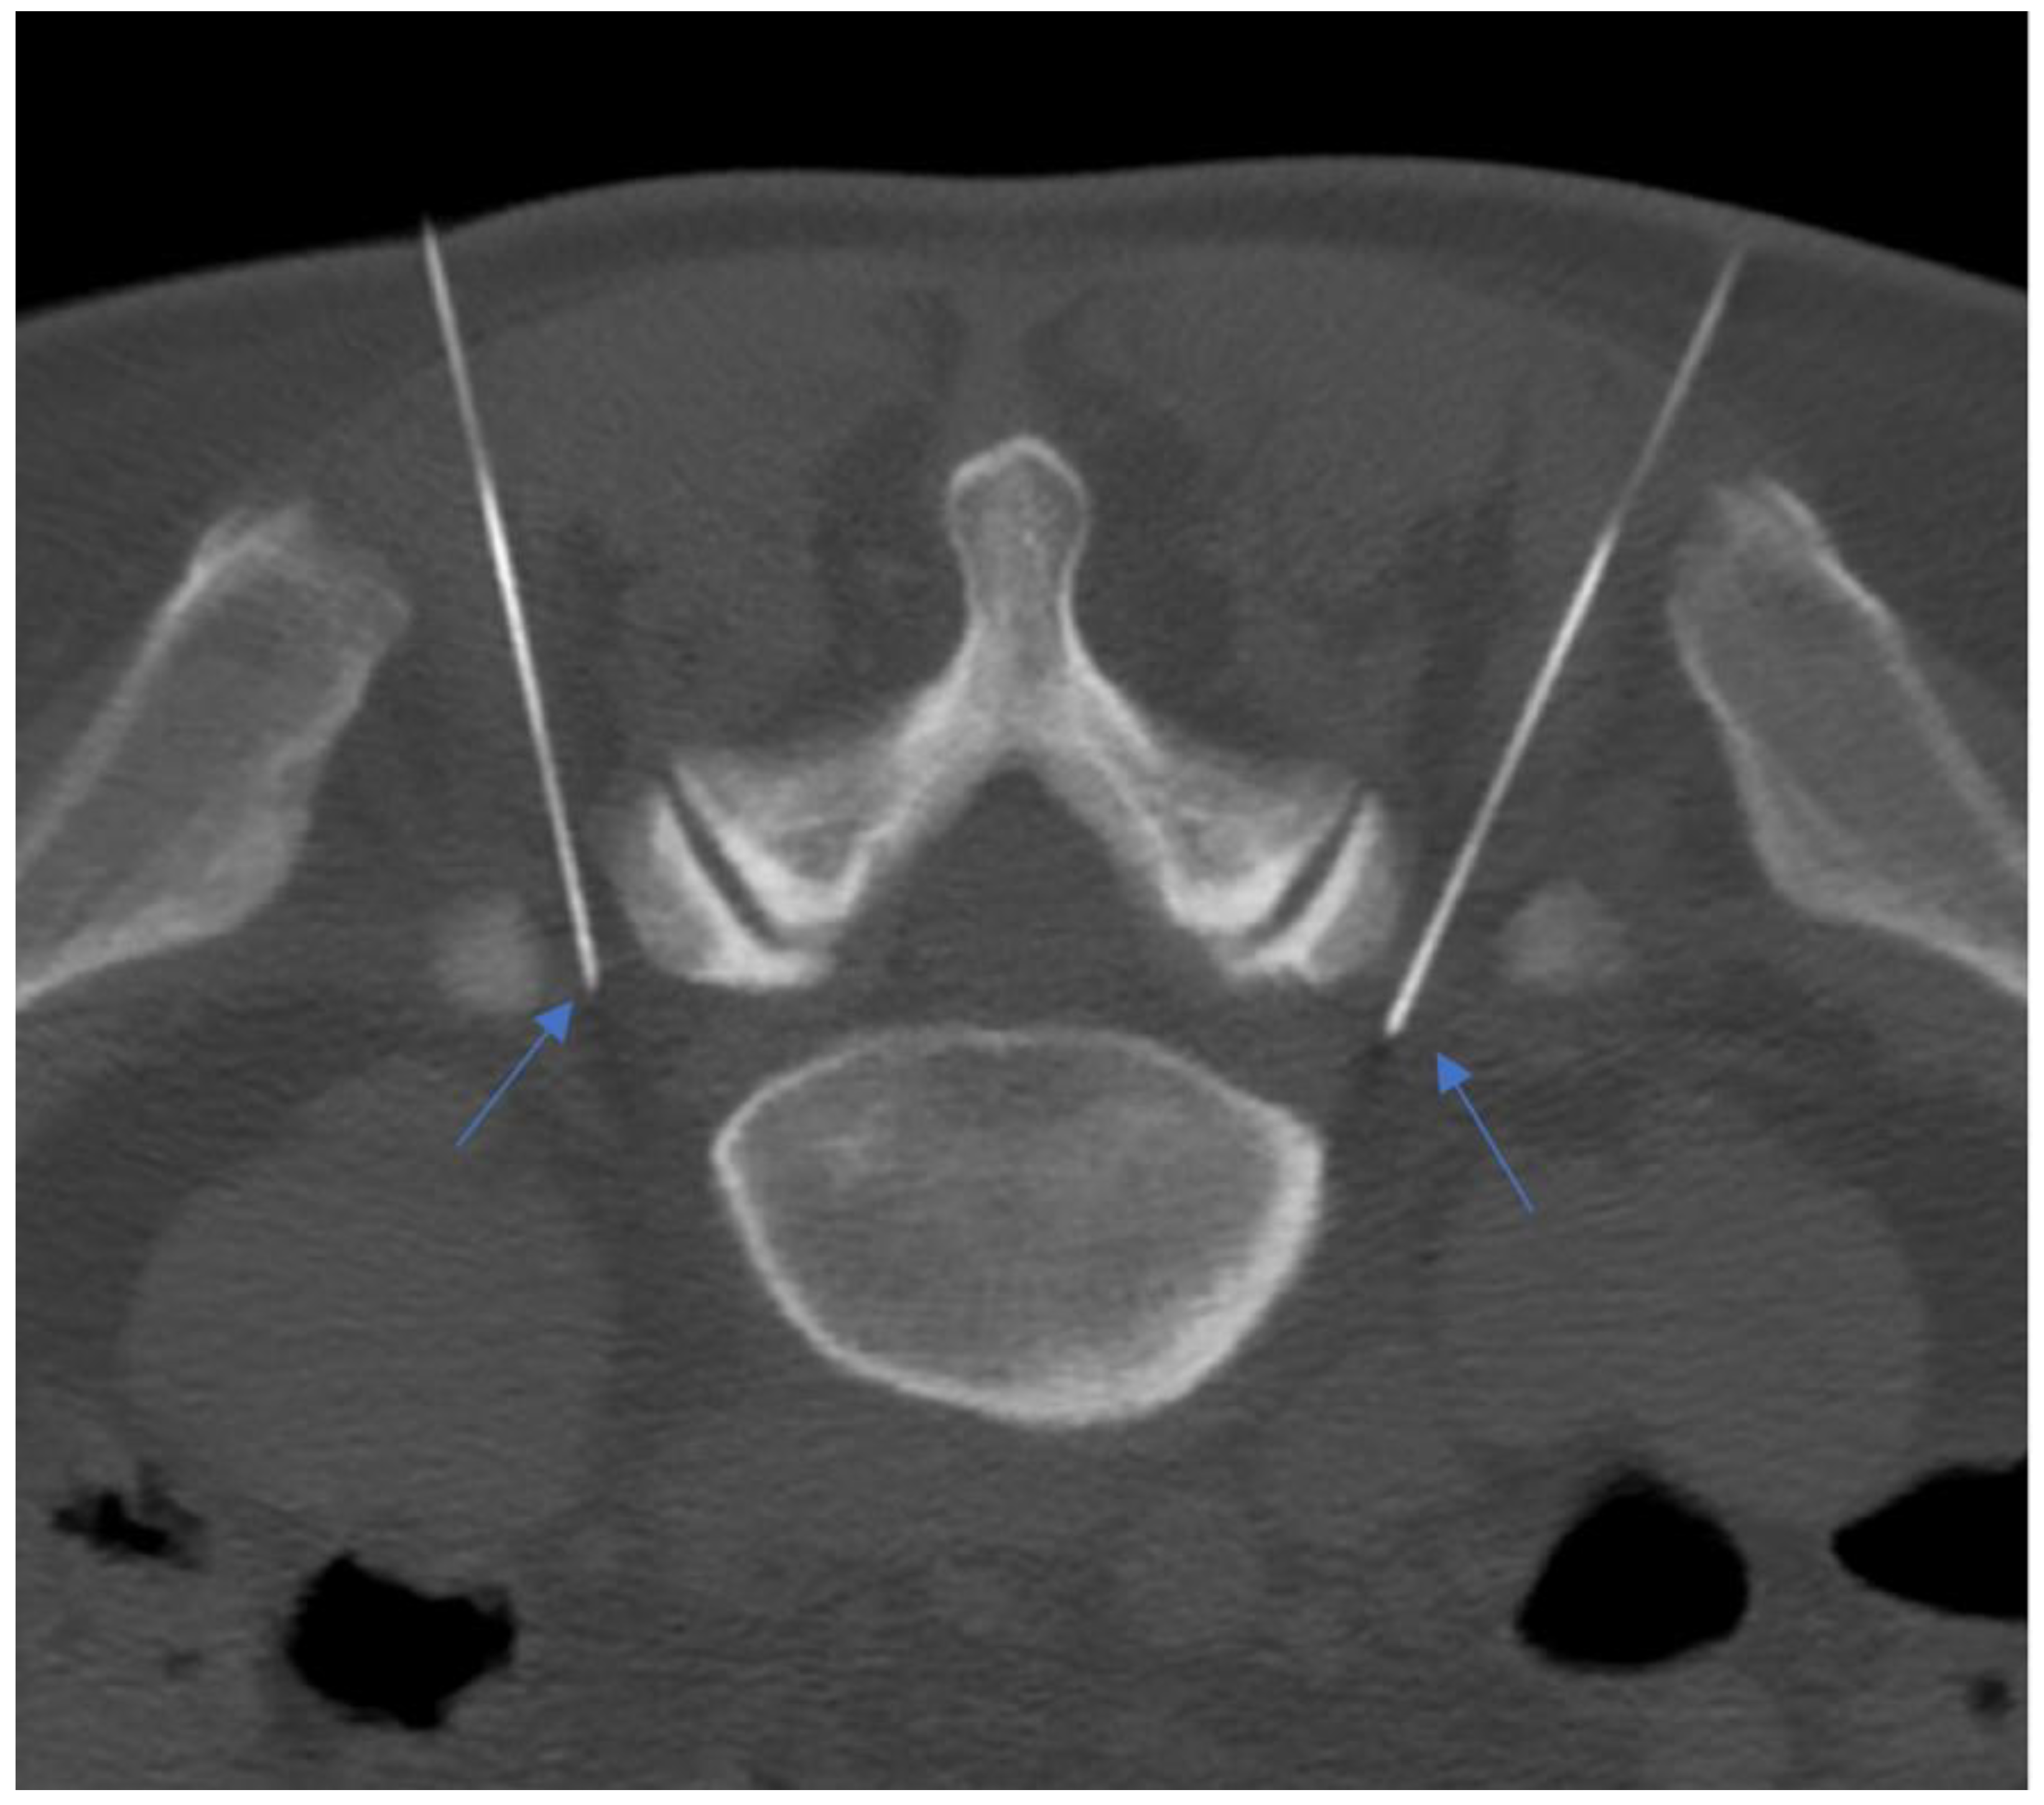

PRF uses intermitted administration of a high-frequency current, allowing heat to disperse to the surrounding tissues, avoiding a temperature rise over the critical level of 42 °C. Typically, RF current (50.000 Hz) is applied in 20 ms pulses, at a frequency of 2 per second for 120 s. A 20–22 G needle electrode with an active tip is introduced and advanced toward the target DRG. The RF current should be activated only if imaging results are confirmed by the exact positioning of the needle on the target symptomatic DRG (Figure 11 and Figure 12) [135,136].

Figure 11.

Ultrasound-guided pulsed radiofrequency treatment of L5 dorsal roots ganglion in a 75-year-old female patient with persistent low back pain and chronic sciatica.

Figure 12.

A 55-year-old patient with lumbosacral discogenic pain treated with bilateral pulsed radiofrequency; the needles are located at around 5 mm close to the L5 ganglion bilaterally (blue arrows).